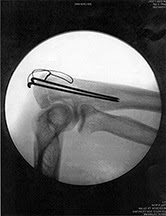

Also posted is the x-ray of the hardware left in my (left) elbow during surgery on Tuesday. Airport security nightmares? We'll see.

I broke my ulna in a spill in the garage last week, fetching bird food and tripped in the pitch black dark on a boat trailer hitch, ouch. So surgery on the elbow tomorrow and had to postpone a few programs, including our trip to Polson, sorry. At least I'll still be able to hoist a camera, hopefully. Thanks Dr. Andy Puckett for fitting me into his incredibly busy schedule. Another photo from the Osprey nest at my sister's in Turah, and look at that power technology. No raccoon in the world would dare climb up there to raid the nest!